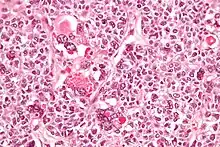

| Micrograph of a juvenile granulosa cell tumour with hyaline globules. H&E stain. | |

Juvenile granulosa cell tumors can be distinguished from adult granulosa cell tumors on histology by their abundant, eosinophilic cytoplasm; primitive, highly mitotic nuclei in polygonal cells; and disorganized follicles.[12][13]